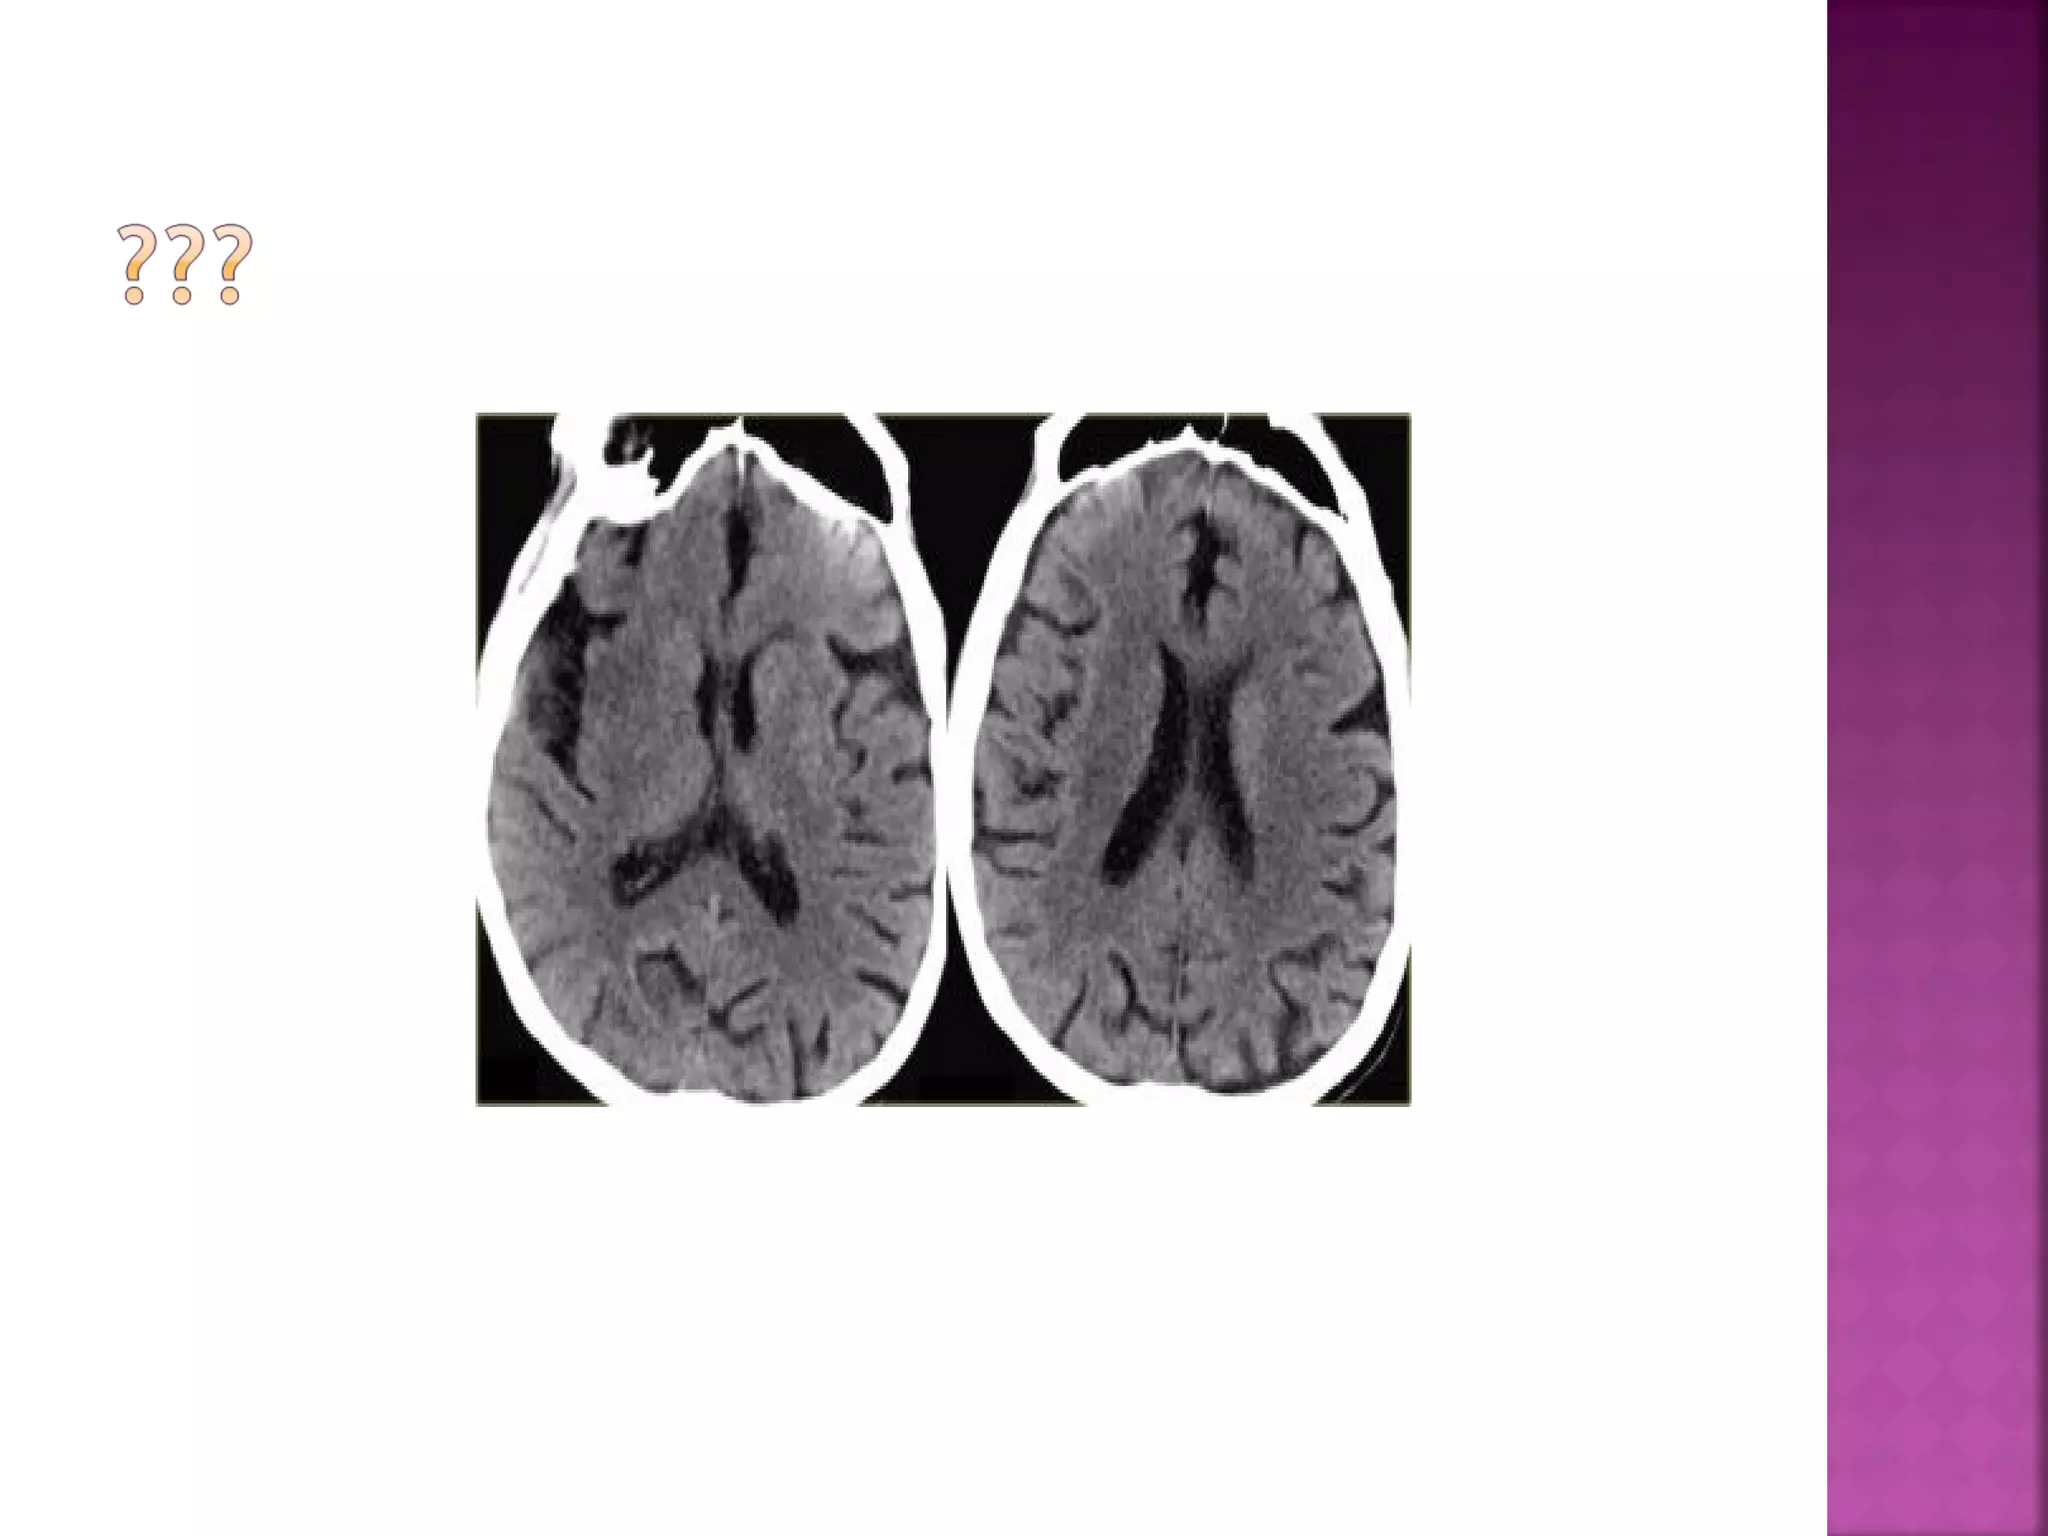

The diagnosis is infarction, because of the

location (vascular territory of the middle

cerebral artery (MCA) and because of the

involvement of gray and white matter, which

is also very typical for infarction.

Obscuration of the lentiform nucleus, also

called blurred basal ganglia, is an important

sign of infarction.

It is seen in middle cerebral artery infarction

and is one of the earliest and most

frequently seen signs.

The basal ganglia are almost always involved

in MCA-infarction.

This refers to hypodensity and swelling of the

insular cortex.

It is a very indicative and subtle early CTsign of infarction in the territory of the

middle cerebral artery.

It has to be differentiated from herpes

encephalitis.